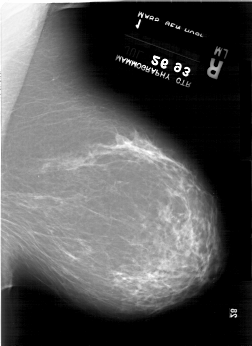

A_1918_1.RIGHT_MLO

RIGHT_MLO LINES 6556 PIXELS_PER_LINE 4786 BITS_PER_PIXEL 12 RESOLUTION 43.5 NON_OVERLAY